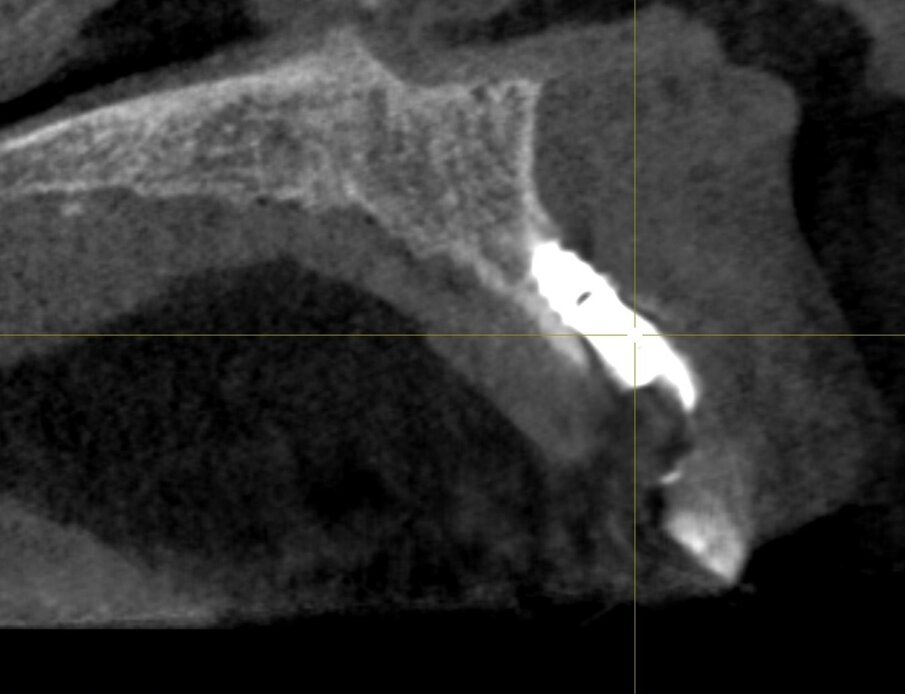

In questo articolo presentiamo un caso clinico che dimostra come il posizionamento improprio di un impianto può rendere impossibile la riabilitazione protesica, che richiede una nuova pianificazione chirurgica e riabilitativa per ottenere l’estetica desiderata. La paziente si presenta alla nostra osservazione con una riabilitazione protesica incongrua, con flangia in resina, a supporto dentale ed implantare, con la presenza di un impianto in posizione 2.1 vestibolarizzato e con l’emergenza nel fornice, in mucosa alveolare. Dalla valutazione della Tac si evince la posizione errata dell’impianto e la perdita consistente in senso trasversale della compagine ossea (Figg. 1, 2). Pertanto si opta per il seguente piano di trattamento che prevede: rimozione dell’impianto e preparazione protesica dell’elemento 2.3, confezionamento di un primo provvisorio a supporto dentale che servirà a guidare la guarigione dei tessuti (Figg. 3-7). A distanza di 4 mesi si procede a un innesto epitelio connettivale libero con prelievo dal palato per compensare il gap dei tessuti molli in senso trasversale, quindi viene ribasato il provvisorio in modo tale da favorire la guarigione dei tessuti (Figg. 8-11). A 9 mesi dalla maturazione dei tessuti si procede alla finalizzazione protesica fissa a supporto dentale (Figg. 12-14).

Fig. 2 - Tac che evidenzia la vestibolarizzazione dell’impianto.